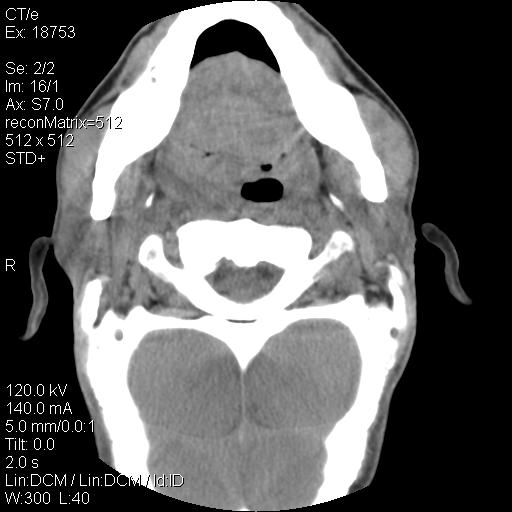

标题: CT21693:男 58岁 右侧咽部疼她2天余 PE:右侧扁桃体肿大 压痛 [打印本页]

标题: CT21693:男 58岁 右侧咽部疼她2天余 PE:右侧扁桃体肿大 压痛

右化脓性扁桃体炎症伴咽后壁脓肿形成.

弥漫性肿胀,与周围组织分界不清,发病急,有明显症状,考虑:感染性病变!

结合病史,考虑感染性病变;建议抗炎治疗复查排除肿瘤性病变。